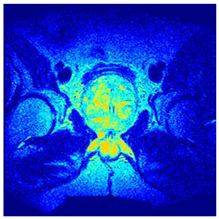

| Image | nt = 3 | nt = 4 | nt = 5 | nt = 8 |

|---|---|---|---|---|

| 1 | ![]() | ![]() | ![]() | ![]() |

| 2 | ![]() | ![]() | ![]() | ![]() |

| 3 | ![]() | ![]() | ![]() | ![]() |

| 4 | ![]() | ![]() | ![]() | ![]() |

| 5 | ![]() | ![]() | ![]() | ![]() |

| 6 | ![]() | ![]() | ![]() | ![]() |

| 7 | ![]() | ![]() | ![]() | ![]() |

| 8 | ![]() | ![]() | ![]() | ![]() |

| 9 | ![]() | ![]() | ![]() | ![]() |

| 10 | ![]() | ![]() | ![]() | ![]() |

| 11 | ![]() | ![]() | ![]() | ![]() |